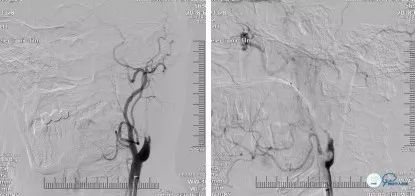

DSA(2018-06-11):右颈内动脉C4-C6段管壁不光滑,多发斑块形成,存在多发串联狭窄;右侧大脑前动脉A1纤细,显影浅淡,右侧大脑中动脉通过软脑膜支向右侧大脑前动脉代偿供血,前交通动脉开放欠佳;左颈内动脉C1段长节段闭塞,局部可见血栓影,左侧颈内动脉C6段以远经眼动脉代偿供血,可见浅淡显影,左侧大脑中动脉、左侧大脑前动脉未见显影;左锁骨下动脉造影可见左侧大脑后动脉通过软脑膜支向左侧大脑中动脉、左侧大脑前动脉代偿供血,左侧后交通未见开放(图5)